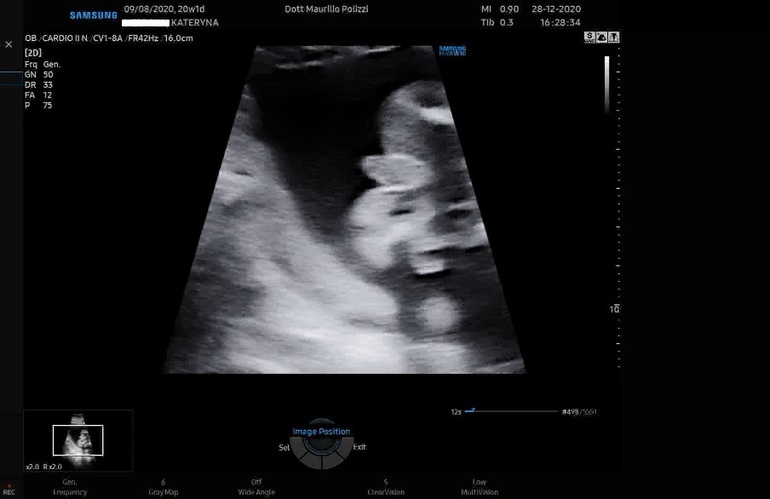

Ура! Второй скрининг пройден!!! Ииии у нас будет футболист))) ещё один сынок 🥰🥰🥰🥰 жить мне в окружении прекрасных мужчин 😍❤🥰🎉 я счастлива, т.к. с самого начала хотела сына, но предчувствие было, что внутри девочка, но сегодняшнее узи опровергло мои ощущения. Сын несказанно рад, прыгает от счастья, муж хотел дочку))) но сыну тоже рад конечно же.

Сынок развивается хорошо, опережает на несколько дней.

Пдр по кд 16.05, по первому скринингу 12.05, по второму скринингу 13.05

Данные с узи:

Ктр 16 см (рост около 22см)

Бпр 46 мм

ОГ 181 мм

ОЖ 150 мм

ДБК 33 мм

Вес 355 г

Фото с узи

Подтверждение пола))